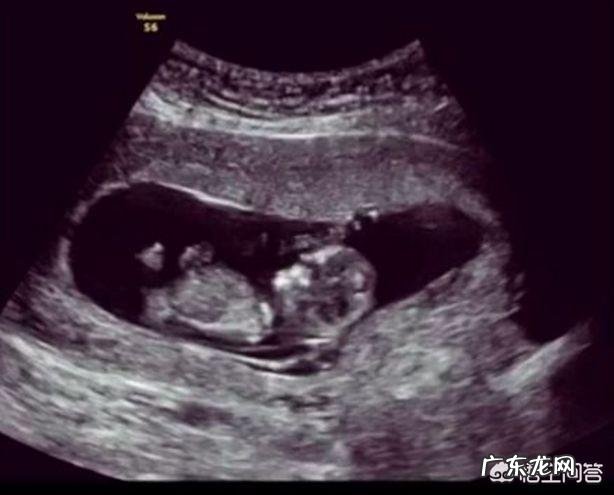

怀孕18周,也就是4个多月,此时胎宝宝还很小,身长大概才23cm,体重300克左右,不过别看宝宝小,其实他们已经会各种乱动的 。

怀孕十八周,胎儿大约有14cm长,体重200克左右,由于每个受精卵着床的位置以及孕妈咪子宫内的情况不同,再加上胎儿一直处于不断活动的过程,因此,怀孕十八周胎儿在孕妈咪肚子里的位置是不确定的 。

虽然怀孕18周胎儿的位置并不固定,但从宫高来看,我们可以把胎儿的位置固定在一个范围:即耻骨联合处和肚脐之间的位置 。怀孕18周,子宫上升,因此,胎儿的位置可能靠近肚脐更多一些 。